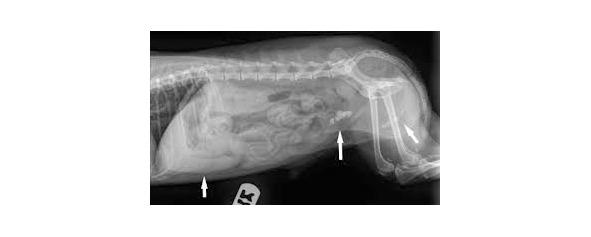

Мал.4. Сечовий апарат котів і собакНачало формы

Мал.5. Сечокам’яна хвороба у собак (МКБ)

Якщо консервативне лікування СКХ у собак неефективне, вживають оперативне втручання. Коли камені неможливо розчинити або вивести природним шляхом, їх видаляють хірургічним шляхом. Великий камінь, перекривший сечовивідні протоки, треба терміново видалити в першучергу. Буває, що незважаючи на усі зусилля, обструкції відбуваються регулярно. Тоді хірург розширить уретру або навіть утворить новий шлях виведення сечі. У псів нерідко видаляють пеніс і розширюють уретру. Після операції дрібні конкременти більше не будуть призводити до закупорки. Однак камені все рівно будуть утворюватися з часом, тобто знадобиться подальше лікування.

Результат багато в чому буде залежати від кваліфікації ветеринара. СКХ підступна, не завжди відразу зрозумілі істинні причини недуги. Часто перша призначена схема не допомагає собаці. Тому треба знайти грамотного фахівця, який буде терпляче спостерігати вашого вихованця протягом тривалого часу, беручи до уваги найдрібніші погіршення його стану і наполегливо добиваючись тривалих ремісій.